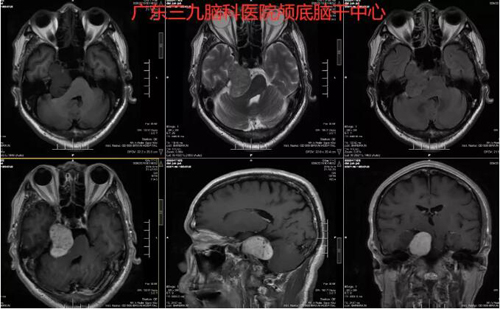

图2:术前MR示右侧三叉神经走行区跨中后颅窝示一团块状占位性病变,呈稍长T1等T2异常信号影,FLAIR序列呈等信号,增强后呈明显稍不均匀异常强化影,大小约为4.4cm×2.8cm×3.6cm,脑干受压,四脑室变窄。右侧丘脑示斑片状长T1长T2异常信号影,FLAIR序列呈高信号。双侧大脑半球皮层下白质内及双侧放射冠区示少许斑点状等T1长T2异常信号影,FLAIR序列呈高信号。